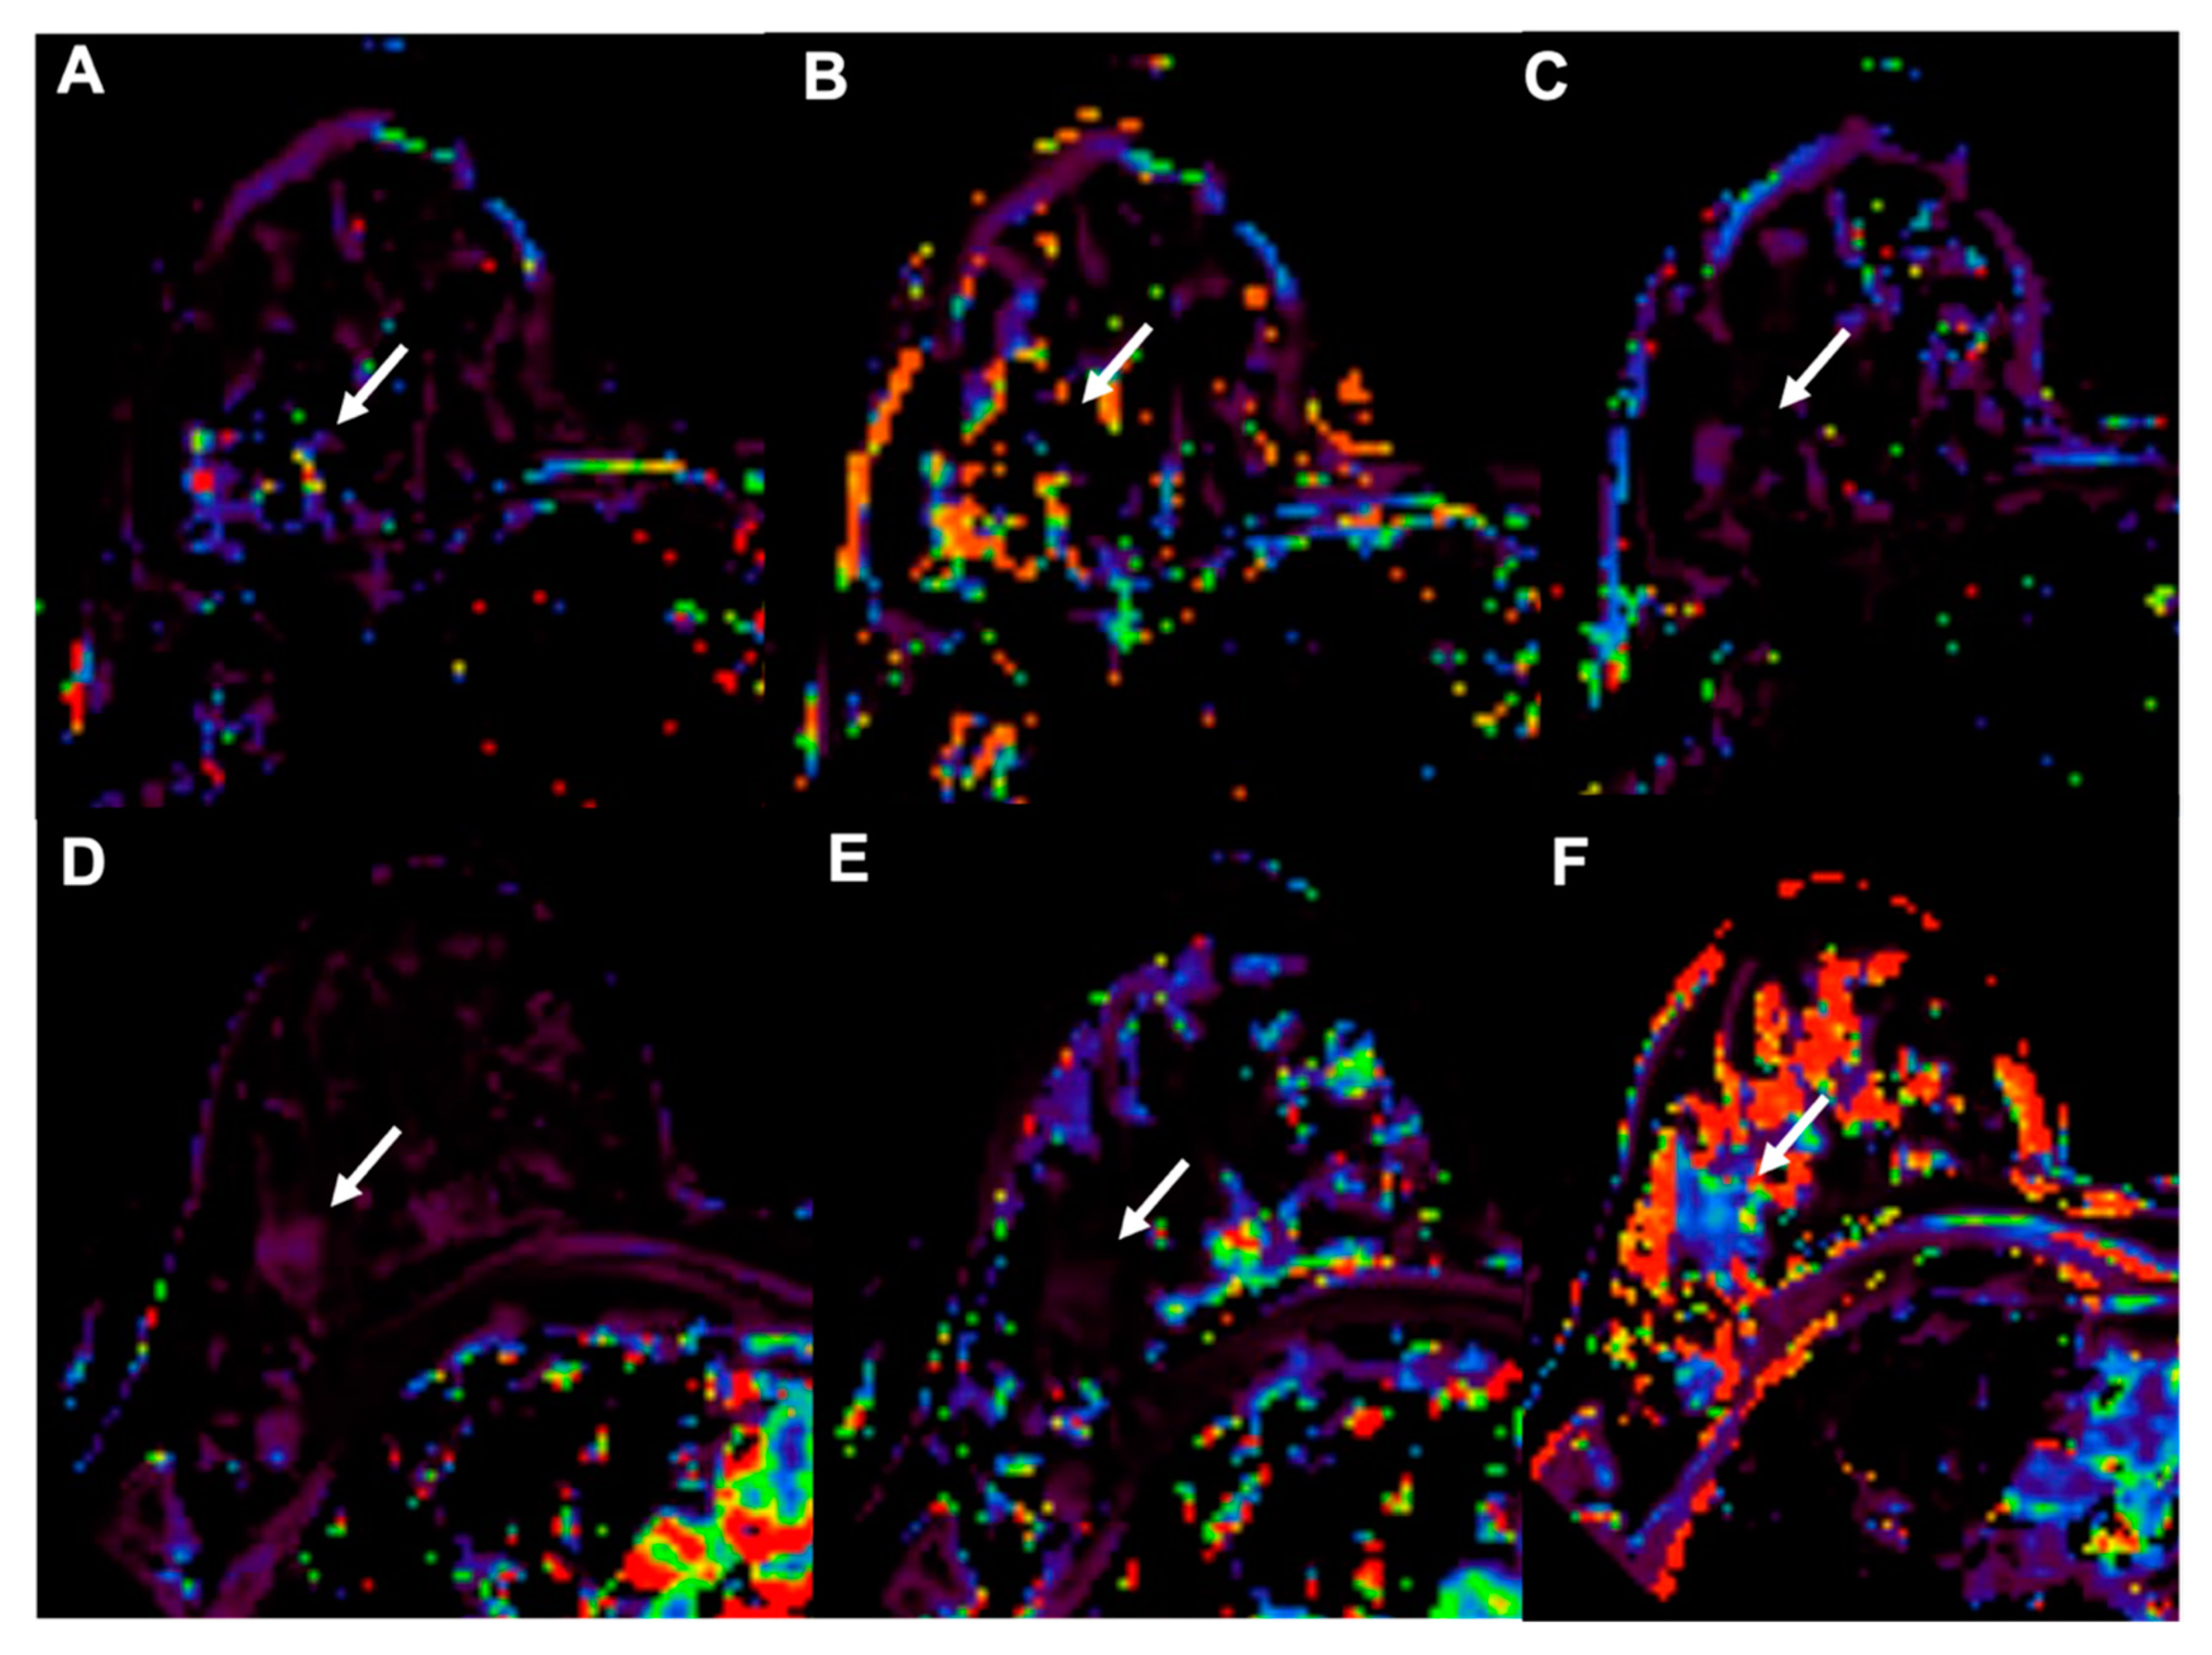

- Sadeghi-Naini, A.; Papanicolau, N.; Falou, O.; Zubovits, J.; Dent, R.; Verma, S.; Trudeau, M.; Boileau, J.F.; Spayne, J.; Iradji, S.; et al. Quantitative Ultrasound Evaluation of Tumor Cell Death Response in Locally Advanced Breast Cancer Patients Receiving Chemotherapy. Clin. Cancer Res. 2013, 19, 2163–2174. [Google Scholar] [CrossRef] [PubMed]

- Klimonda, Z.; Karwat, P.; Dobruch-Sobczak, K.; Piotrzkowska-Wroblewska, H.; Litniewski, J. Breast-lesions characterization using Quantitative Ultrasound features of peritumoral tissue. Sci. Rep. 2019, 9, 7963. [Google Scholar] [CrossRef]

- Piotrzkowska-Wroblewska, H.; Dobruch-Sobczak, K.; Klimonda, Z.; Karwat, P.; Roszkowska-Purska, K.; Gumowska, M.; Litniewski, J. Monitoring breast cancer response to neoadjuvant chemotherapy with ultrasound signal statistics and integrated backscatter. PLoS ONE 2019, 14, e0213749. [Google Scholar] [CrossRef]